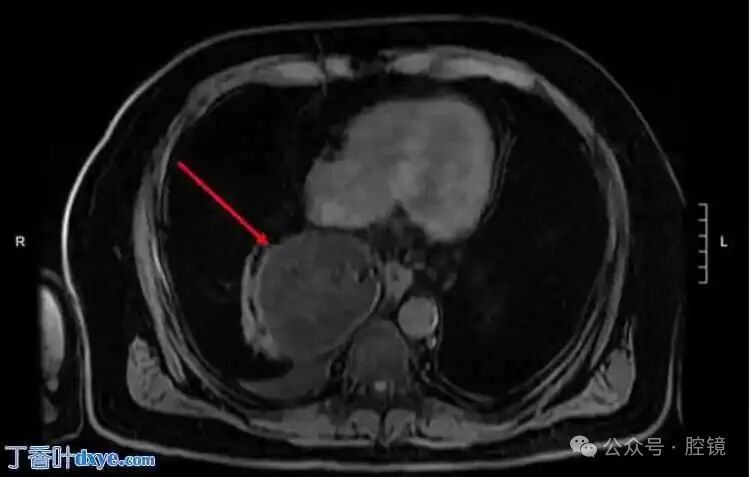

A 65-year-old male presented to the emergency department with a complaint of upper abdominal pain for 48 hours, radiating to the back. His medical history indicated a 5 cm ascendingaortic aneurysm. The patient had no previous surgical history and no significant family history. He exhibited no fever, normal blood pressure, and tachycardia. Physical examination revealed tenderness in the upper abdomen with muscle rigidity, but no rigidity or rebound tenderness. A non-contrast spiral abdominal CT scan showed a soft tissue mass just above the gastroesophageal junction, requiring differential diagnosis with a lipoma or liposarcoma (Figure 1-2). Due to the unclear diagnosis, the physician arranged for a chest MRI. The MRI revealed a large omental hernia through the esophageal hiatus (Figure 3-4), with fluid around the herniated omentum, suggesting strangulation. In the sagittal view of the MRI, the abdominal omentum was seen entering the thoracic cavity (Figure 2-4).Figure 1. Cross-sectional view showing a lipomatous mass behind the heart, with surrounding fluid consistent with strangulated lesions.

Figure 4. Sagittal view: the herniated area is located on the dorsal side of the diaphragm.